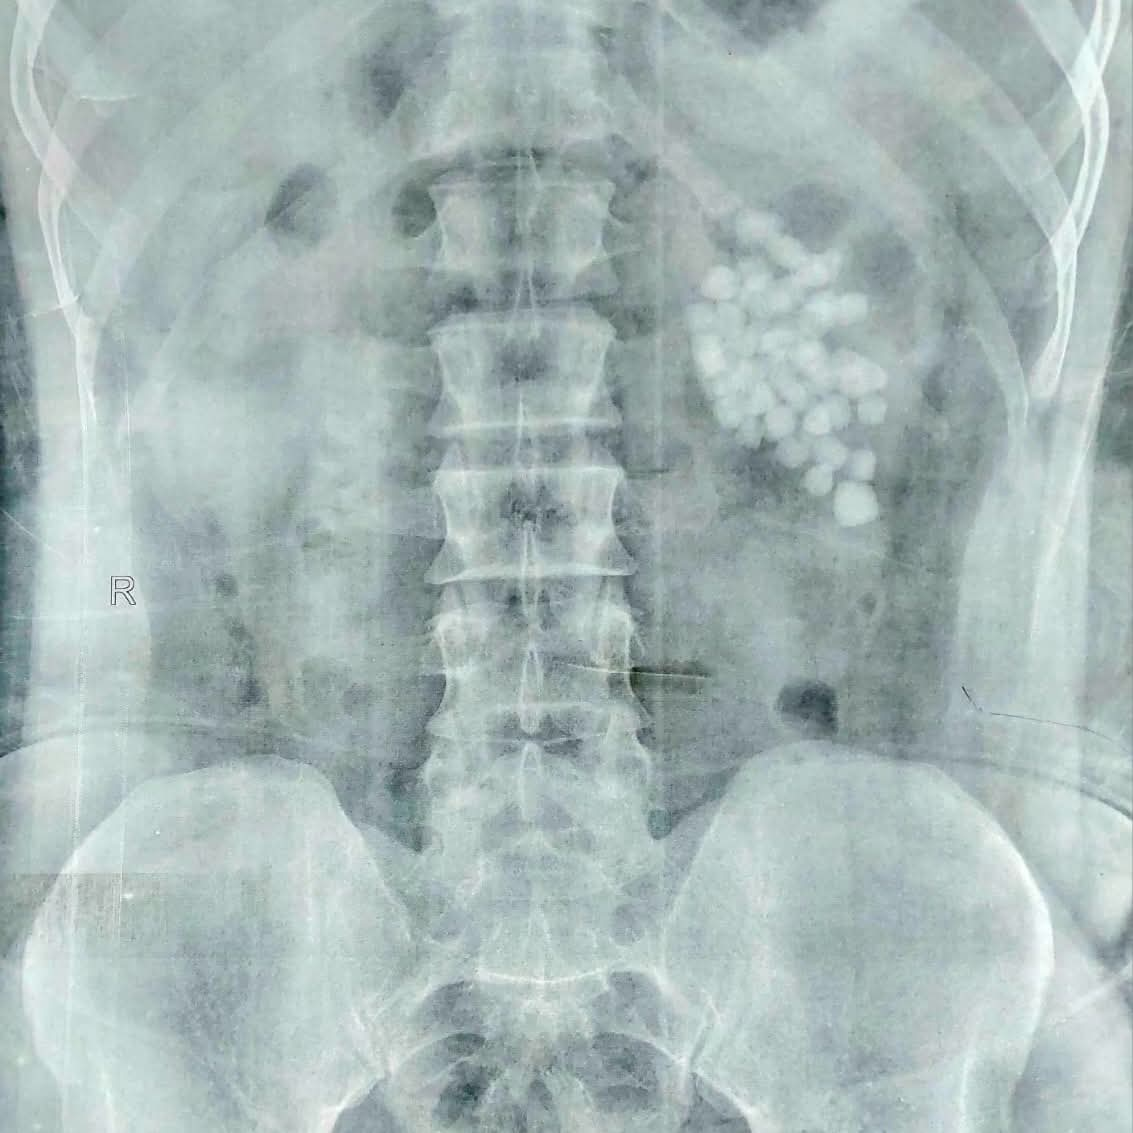

عملية استغرقت ساعتين.. استخراج 58 حصوة من كلية مريض بمستشفى قنا الجامعي

أعلنت مستشفيات قنا الجامعية، نجاح فريق طبي متخصص بمستشفى المعبر الجامعي، في إجراء عملية دقيقة لاستخراج 58 حصوة من الكلية اليسرى لمريض يبلغ من العمر 40 عامًا، وذلك باستخدام أحدث تقنيات مناظير الكلى المتقدمة.

وأوضح الأستاذ الدكتور مصطفى عبد الرازق رئيس قسم المسالك البولية، أن المريض وصل وهو يعاني من آلام متكررة وارتفاع في نسبة الأملاح، وبفحصه تبيّن وجود عدد كبير من الحصوات المتجمعة في حوض الكلية اليسرى، ما استدعى التدخل الجراحي حفاظًا على وظائف الكلية.

وأشار إلى أنه تم تجهيز المريض وإخضاعه للتخدير العام، ثم البدء في العملية من خلال فتحة صغيرة لا تتجاوز سنتيمترًا واحدًا للوصول إلى الكلية، قبل تفتيت الحصوات باستخدام تقنيات التفتيت الهوائي والليزر تبعًا لطبيعة كل حصوة.

واستمرت العملية نحو ساعتين، تمكن خلالها الفريق الطبي من إزالة جميع الحصوات والتأكد من تنظيف حوض الكلية بالكامل، مع تركيب أنبوب تصريف مؤقت لضمان خروج السوائل بصورة آمنة.